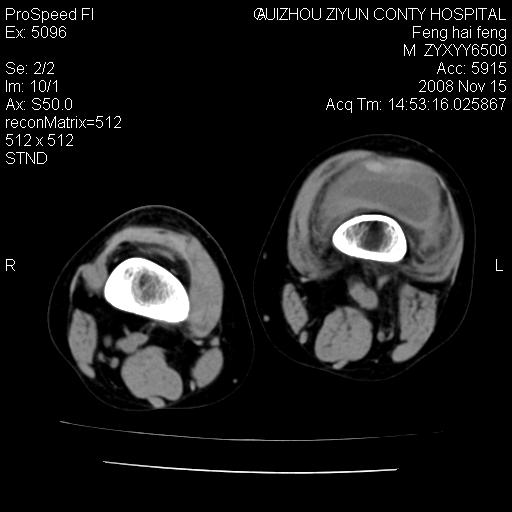

标题: CT16656:M 14Y 左膝关节肿胀一年余。其余病史不详。 [打印本页]

标题: CT16656:M 14Y 左膝关节肿胀一年余。其余病史不详。

考虑左侧髌骨结核;左膝关节滑膜肿胀、增厚,关节囊积液。

左膝滑膜型关节结核可能性大!支持!滑膜型关节结核主要ct表现:关节囊肿胀,积液,关节面见小破坏灶,并见点状死骨!

好大的左腿!考虑左侧髌骨结核,左膝关节滑膜肿胀、增厚,关节囊积液。

左侧髌骨结核;左膝关节滑膜肿胀、增厚,关节囊积液